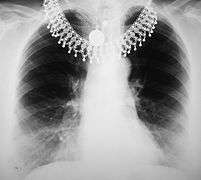

Chest x-ray